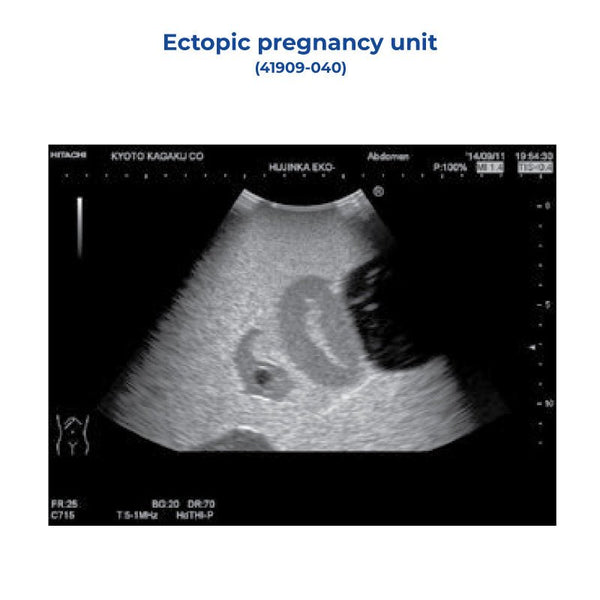

Reproductive impact of local CIN treatment, ectopic-pregnancy-unit-kk-,

ectopic-pregnancy-unit-kk-, Full article: Physical activity during pregnancy and adverse,